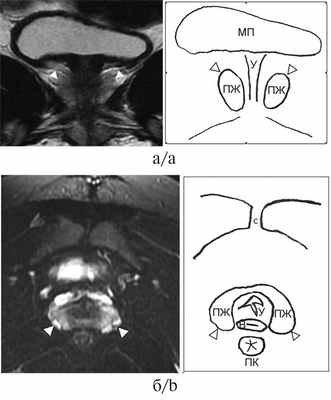

С целью определения объема и тактики оперативного лечения в обоих случаях проведено магнитно-резонансное томографическое (МРТ) исследование органов малого таза без контрастирования в режимах Т1, Т2, DW, выполненное на оборудовании Optima MR450w №415449 («GE Healthcare», США). В области уретры, проксимальнее уретровагинального конфлюенса выявлена ткань ПЖ, имеющая небольшой объем и отсутствие зональной дифференцировки. На МР-изображениях ткань ПЖ располагается типично для мужской ПЖ в парауретральной области, за лобковым симфизом, книзу от мочевого пузыря, эллипсоидной формы, представлена преимущественно железистой тканью периферической зоны, однородной структуры с гиперинтенсивным гомогенным сигналом в режиме Т2-ВИ и изоинтенсивным сигналом в режиме Т1-ВИ (рис. 1, 2). Комплексное уродинамическое исследование (КУДИ) не выявило признаков инфравезикальной обструкции (см. табл. 2). При цистоуретровагиноскопии, проведенной непосредственно перед операцией, выявлены высокий уретровагинальный конфлюенс и признаки гранулярного цистита в области треугольника Льетто у обеих девочек. Особенностью патологического строения мочеполовых путей у пациентки 2 явилось резкое сужение входа во влагалище. Последний открывался отверстием диаметром 0,3 см, окруженным складкой слизистой (гименальным кольцом) над уровнем тазовой диафрагмы. Показания к проведению второго этапа феминизации у пациентки 1 обоснованы в связи с наступлением первой менструации и достаточной эстрогенизацией гениталий [3]. Пациентка 2 не достигла менархе. С учетом эндоскопической находки в виде резкого сужения входа во влагалище и риска развития клиники гематокольпос и гематометра при наступлении менархе в будущем вследствие нарушения оттока менструальных выделений принято решение о проведении второго этапа феминизации. Пациенткам проведена разобщающая мочевые и половые пути интроитопластика. Выполнена полная мобилизация общего мочеполового канала (ОМК) с формированием передней стенки искусственного входа во влагалище (ИВВ) слизистым лоскутом в модификации Passorini—Glasel. Задняя стенка ИВВ сформирована с помощью омега-образного кожного лоскута промежности. Неоуретра и неомеатус сформированы из участка ОМК. Пациентки выписаны из стационара в удовлетворительном состоянии на 9-е и 11-е сутки после операции. Рекомендовано следующее: гормональная терапия, получаемая пациентками на момент поступления (см. табл. 2); ежеквартальный контроль уровней 17-ОНП, тестостерона, АКТГ и ренина плазмы крови для оценки компенсации глюкокортикоидной и минералокортикоидной недостаточности; наблюдение гинеколога; контрольная МРТ малого таза; уродинамическое исследование через 6—12 мес для оценки результата операции и динамики роста ПЖ; ежегодный контроль уровня простатического специфического антигена (ПСА) и повторная МРТ в случае его увеличения.

Рис. 1. Серия МРТ малого таза в режиме Т2-ВИ со скицами пациентки 1, 17 лет, с диагнозом «ВДКН, сольтеряющая форма».

а — сагиттальная плоскость; б — аксиальная плоскость; в — фронтальная плоскость. На изображениях визуализируются уретра (черная стрелка), влагалище (белая пунктирная стрелка) с наличием в просвете небольшого количества жидкости. Уретровагинальный конфлюенс (белая стрелка) определяется на уровне средней трети симфиза. Круглыми МРТ метками на рис. а обозначены наружное отверстие общего мочеполового канала, расположенное ближе к симфизу, и проекция входа во влагалище, расположенного ближе к прямой кишке. Визуализируется ткань предстательной железы (головки черных стрелок), эллипсоидной формы, без четкой зональной дифференцировки, размерами 34×15×32 мм (объем 8,4 см 3 ) без видимых очаговых изменений в структуре. МП — мочевой пузырь, С — симфиз, У — уретра, В — влагалище, ОМК — общий мочеполовой канал, ПК — прямая кишка, ПЖ — предстательная железа, Д — детрузор мочевого пузыря.

Рис. 2. Серия МРТ малого таза со скицами пациентки 2, 16 лет, с диагнозом «ВДКН, сольтеряющая форма».

а — корональная плоскость в режиме Т2-ВИ; б — аксиальная плоскость в режиме Т2-ВИ с подавлением сигнала от жировой ткани. Визуализируется ткань предстательной железы (белые головки стрелок), эллипсоидной формы, без четкой зональной дифференцировки, размерами 30×14×21 мм (объем 4,6 см 3 ). Структура предстательной железы представлена преимущественно железистой тканью периферической зоны, однородной структуры с гиперинтенсивным гомогенным сигналом без видимых очаговых изменений. МП — мочевой пузырь, С — симфиз, У — уретра, В — влагалище, ПК — прямая кишка, ПЖ — предстательная железа.